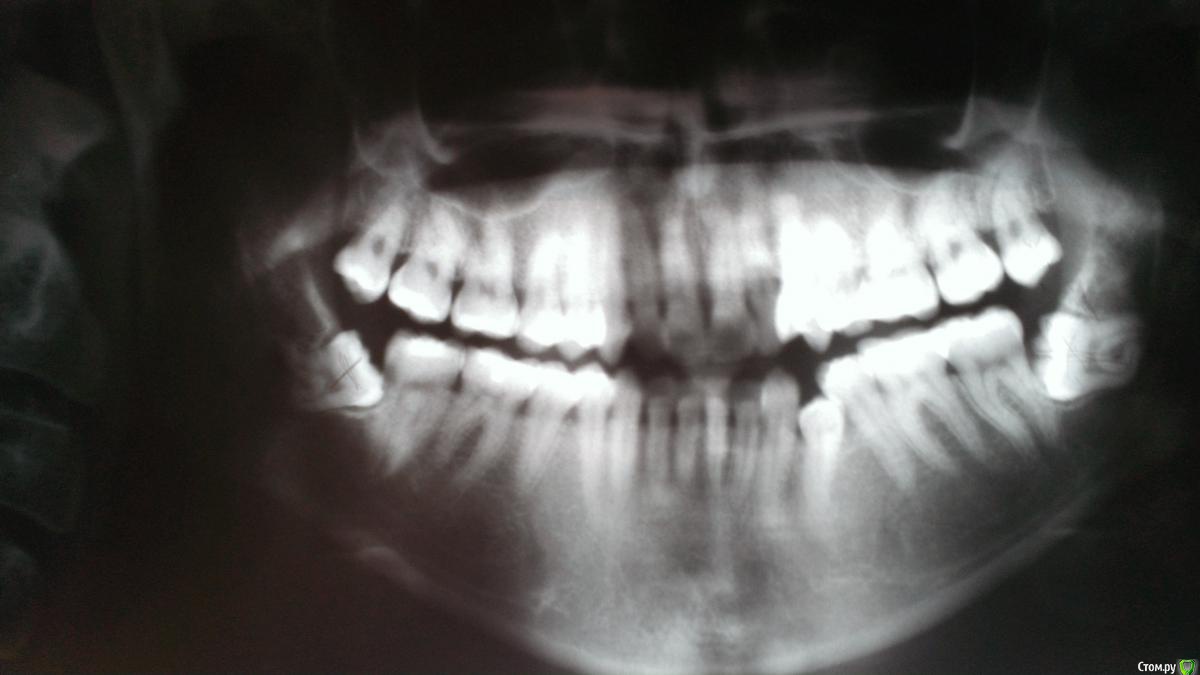

milhki Опубликовано 18 января, 2016 Поделиться Опубликовано 18 января, 2016 (изменено) Здравствуйте, уважаемые врачи! У меня к вам вопрос: как в моем случае лучше удалять нижние восьмерки с использованием пьезо или нет? Под общим наркозом или местным? Вопрос цены не стоит, главное, чтобы все прошло удачно и как можно менее травматично как физически, так и морально))) Летом 2015 начал беспокоить сустав справа, рот сильно широко и долго держать не могу. Насколько сложное удаление и на что надо обратить внимание? Спасибо! Снимки 2015 и 2009 года. Что с семеркой справа? Ее тоже надо будет удалять или полечить возможно, пока она меня никак не беспокоит, но врачи на нее указывали. Снимки худшего качества - лето 2015 года Снимок более темный - 2009 год Изменено 18 января, 2016 пользователем milhki Ссылка на комментарий

Alejandro Опубликовано 19 января, 2016 Поделиться Опубликовано 19 января, 2016 Обе восьмёрки на выход. Без пьезо можно удалить. 1 Ссылка на комментарий